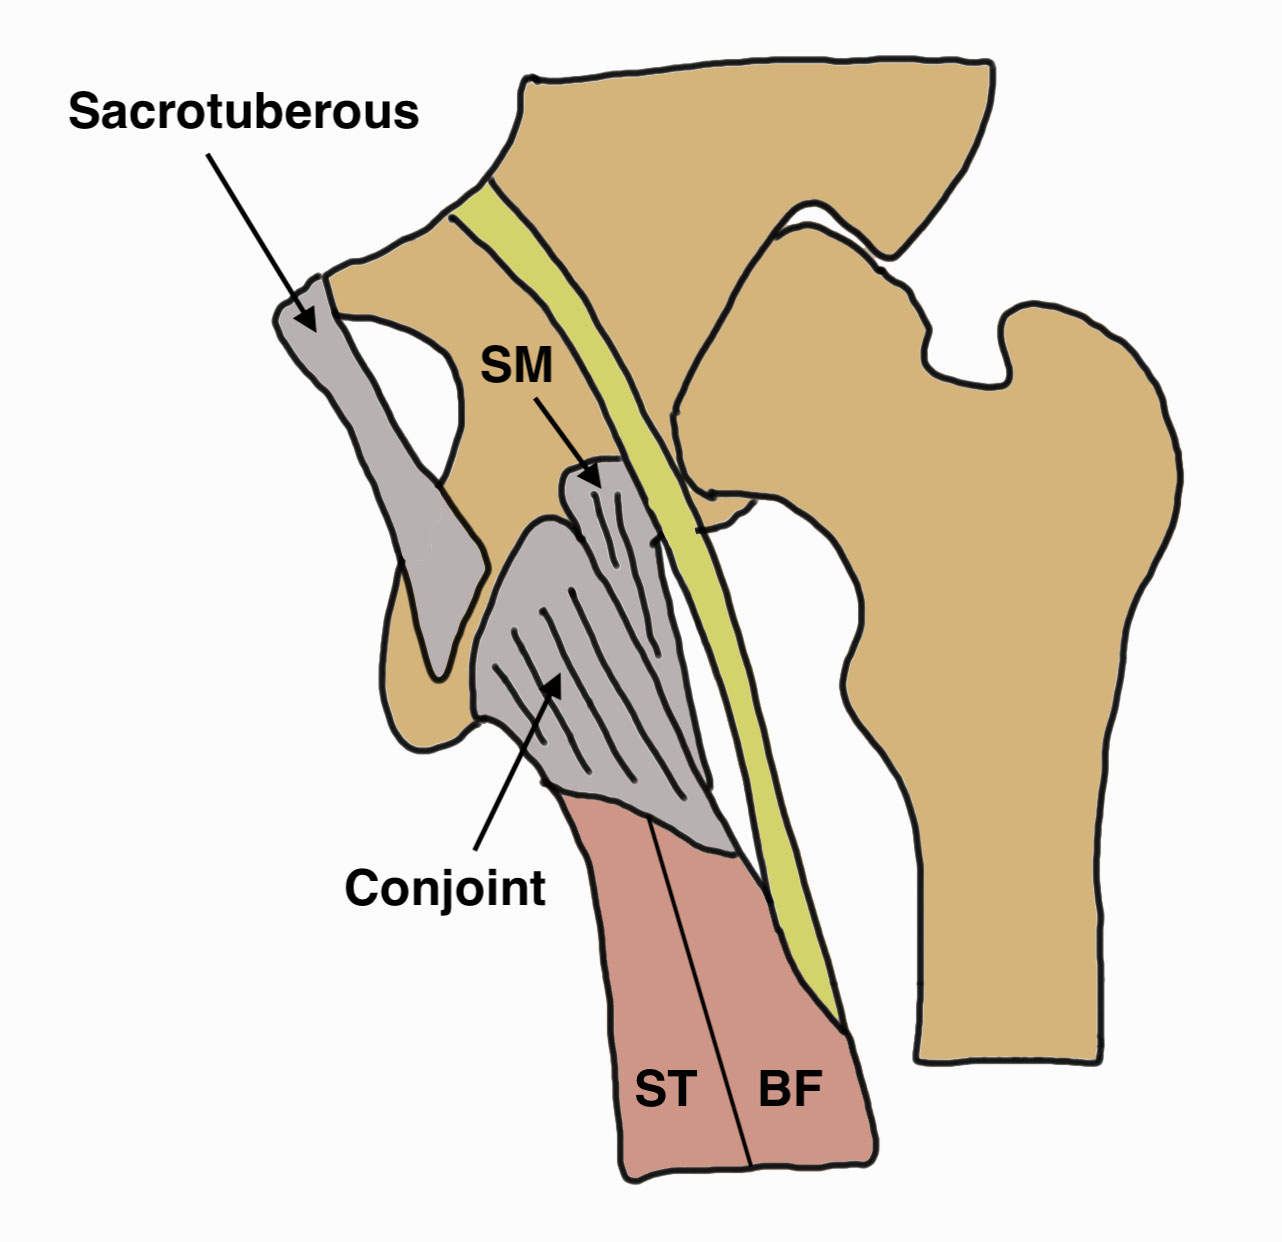

Anatomy

Hamstring by definition originate from the (lateral aspect of) the ischial tuberosity

Conjoint tendon

- biceps femoris and semitendinosus

- posterolateral aspect of the ischial tuberosity

Semimembranosus

- separate attachment

- anterolateral aspect of the ischial tuberosity